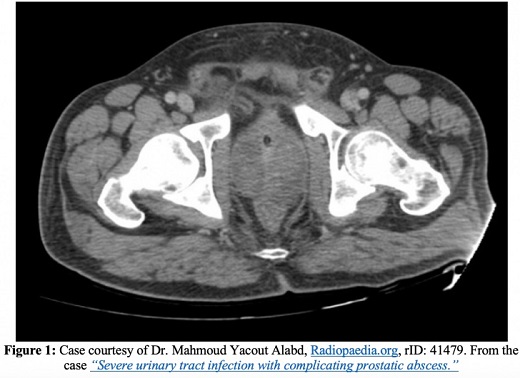

La tomodensitométrie avec et sans contraste intraveineux peut être utile pour déterminer l’étendue de la maladie, c’est-à-dire en relation avec la propagation nécrosante, et constitue la modalité d’imagerie privilégiée pour évaluer les abcès emphysémateux de la prostate.

Outre l’endocardite, l’épididymite, la propagation de l’infection aux espaces osseux ou articulaires et le développement d’une prostatite chronique, l’une des complications les plus graves de la prostatite aiguë est un abcès de la prostate. Sur les images tomodensitométriques, les abcès de la prostate apparaissent comme des collections de liquide non rehaussées. Les abcès prostatiques apparaîtront sous forme de zones anéchoïques ou hypoéchogènes à l’échographie transrectale.